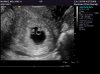

I am in awe. I just got back from u/s where they found TWO heartbeats inside TWO beans!... it's still very very early... and with the spotting earlier (which has subsided)...

Dr informed me that multiples have higher risk for miscarriage, and they didn't see a membrane b/w the two gestational sacks (maybe too early to see at this point in pregnancy).... I go back in two weeks for another u/s.